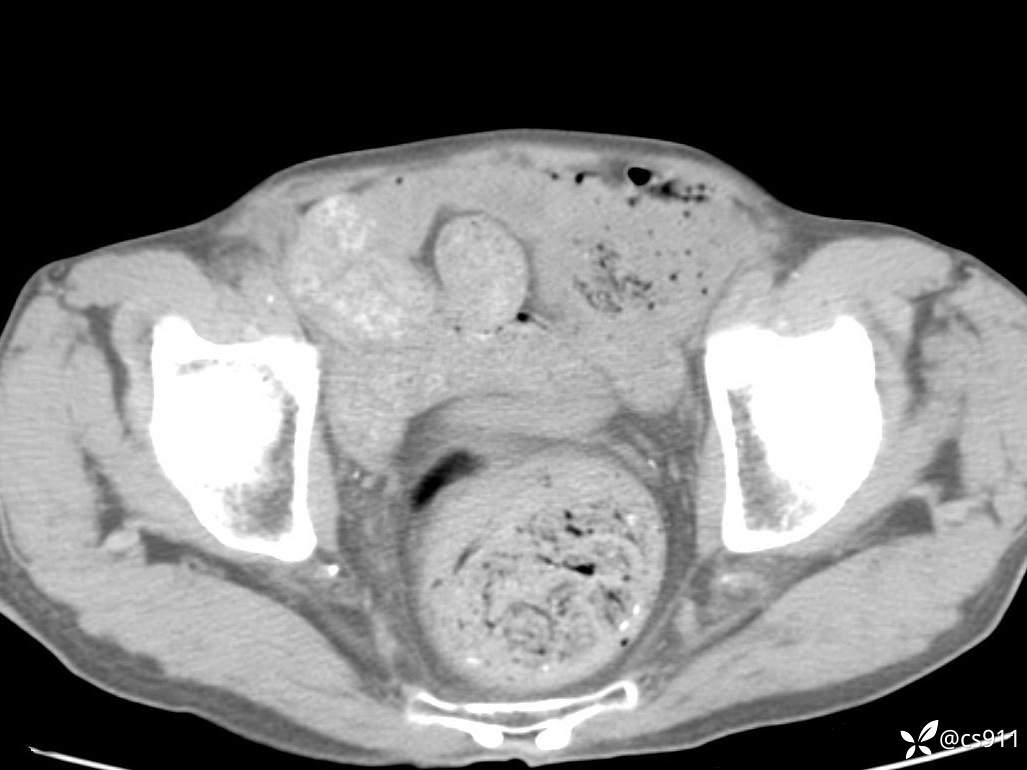

急腹症之急诊CT,原因?答案公布

男,77岁,腹痛、腹胀伴恶心呕吐1天。呕吐胃内容物,非喷射性呕吐,有咖啡色样胃内容物,诉有胃穿孔病史。查体:全腹平,下腹部压痛,全腹无反跳痛,叩诊呈浊音,移动性浊音阴性,肠鸣音减弱,1-2次/分。肛检:直肠未扪及明显肿物,可触及大量粪块。

T 36.6℃ P 80次/分 R 26次/分 BP 100/60mmHg

白细胞(WBC) H 14.55 10e9/L 4-10

红细胞(RBC) 4.58 10e12/L 4.3-5.8

中性粒细胞百分率(NEUT%) H 85.7 % 40-75

血淀粉酶(AMY) HH 1859 U/L 35-135

癌胚抗原(CEA) H 27.44 ng/ml 0-5

呕吐物 潜血试验 * 阳性 阴性

患者轮椅入室检查神志清楚, 能配合摆位和呼吸